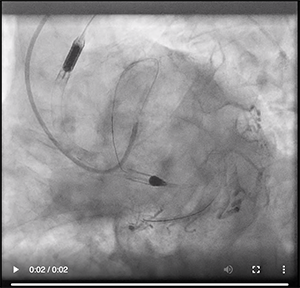

Revascularization seemed appropriate when considering the acute coronary syndrome complicated by VT at presentation, which was probably induced by a large ischemic area. Furthermore, because of his advanced age and high EuroSCORE, we decided to perform percutaneous coronary revascularization of the LM bifurcation lesion (Video 1A, Video 1B). We believed that treating only the LM-LAD would have resulted in worsening of the ostial left circumflex artery, which could cause further ischemia and/or infarction with the risk of VT and/or further reduction of LVEF.

Video 1. Right anterior oblique (A) and spider projections (B) of the LM bifurcation.